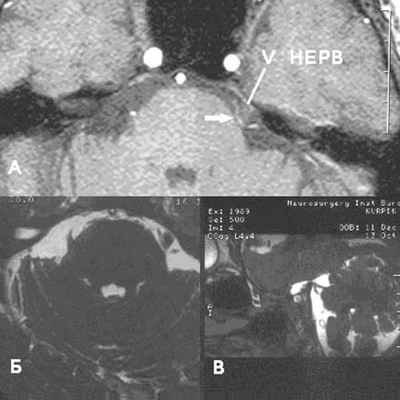

Аксиальный срез (А, Б), сагиттальная проекция (В). Определяется нейроваскулярный конфликт между артерией и тройничным нервом. Компрессия тройничного нерва прилежащей к нему артерией обозначена стрелкой.

У места выхода тройничного нерва из ствола головного мозга (обозначено кругом) определяется крупный артериальный сосуд, компремирующий указанный нерв. На противоположной стороне визуализируется корешок V нерва, на расстоянии от которого проходит аналогичный артериальный сосуд.

Определяется близкое расположение артериального сосуда и лицевого нерва (указано стрелкой), что может являться причиной гемифациального спазма

Определяются признаки компрессии лицевого нерва около ствола головного мозга крупным артериальным сосудом – позвоночной артерией (указано стрелкой).

Визуализируется близкое расположение артериального сосуда и лицевого нерва (указано стрелкой), что может являться причиной гемифациального спазма